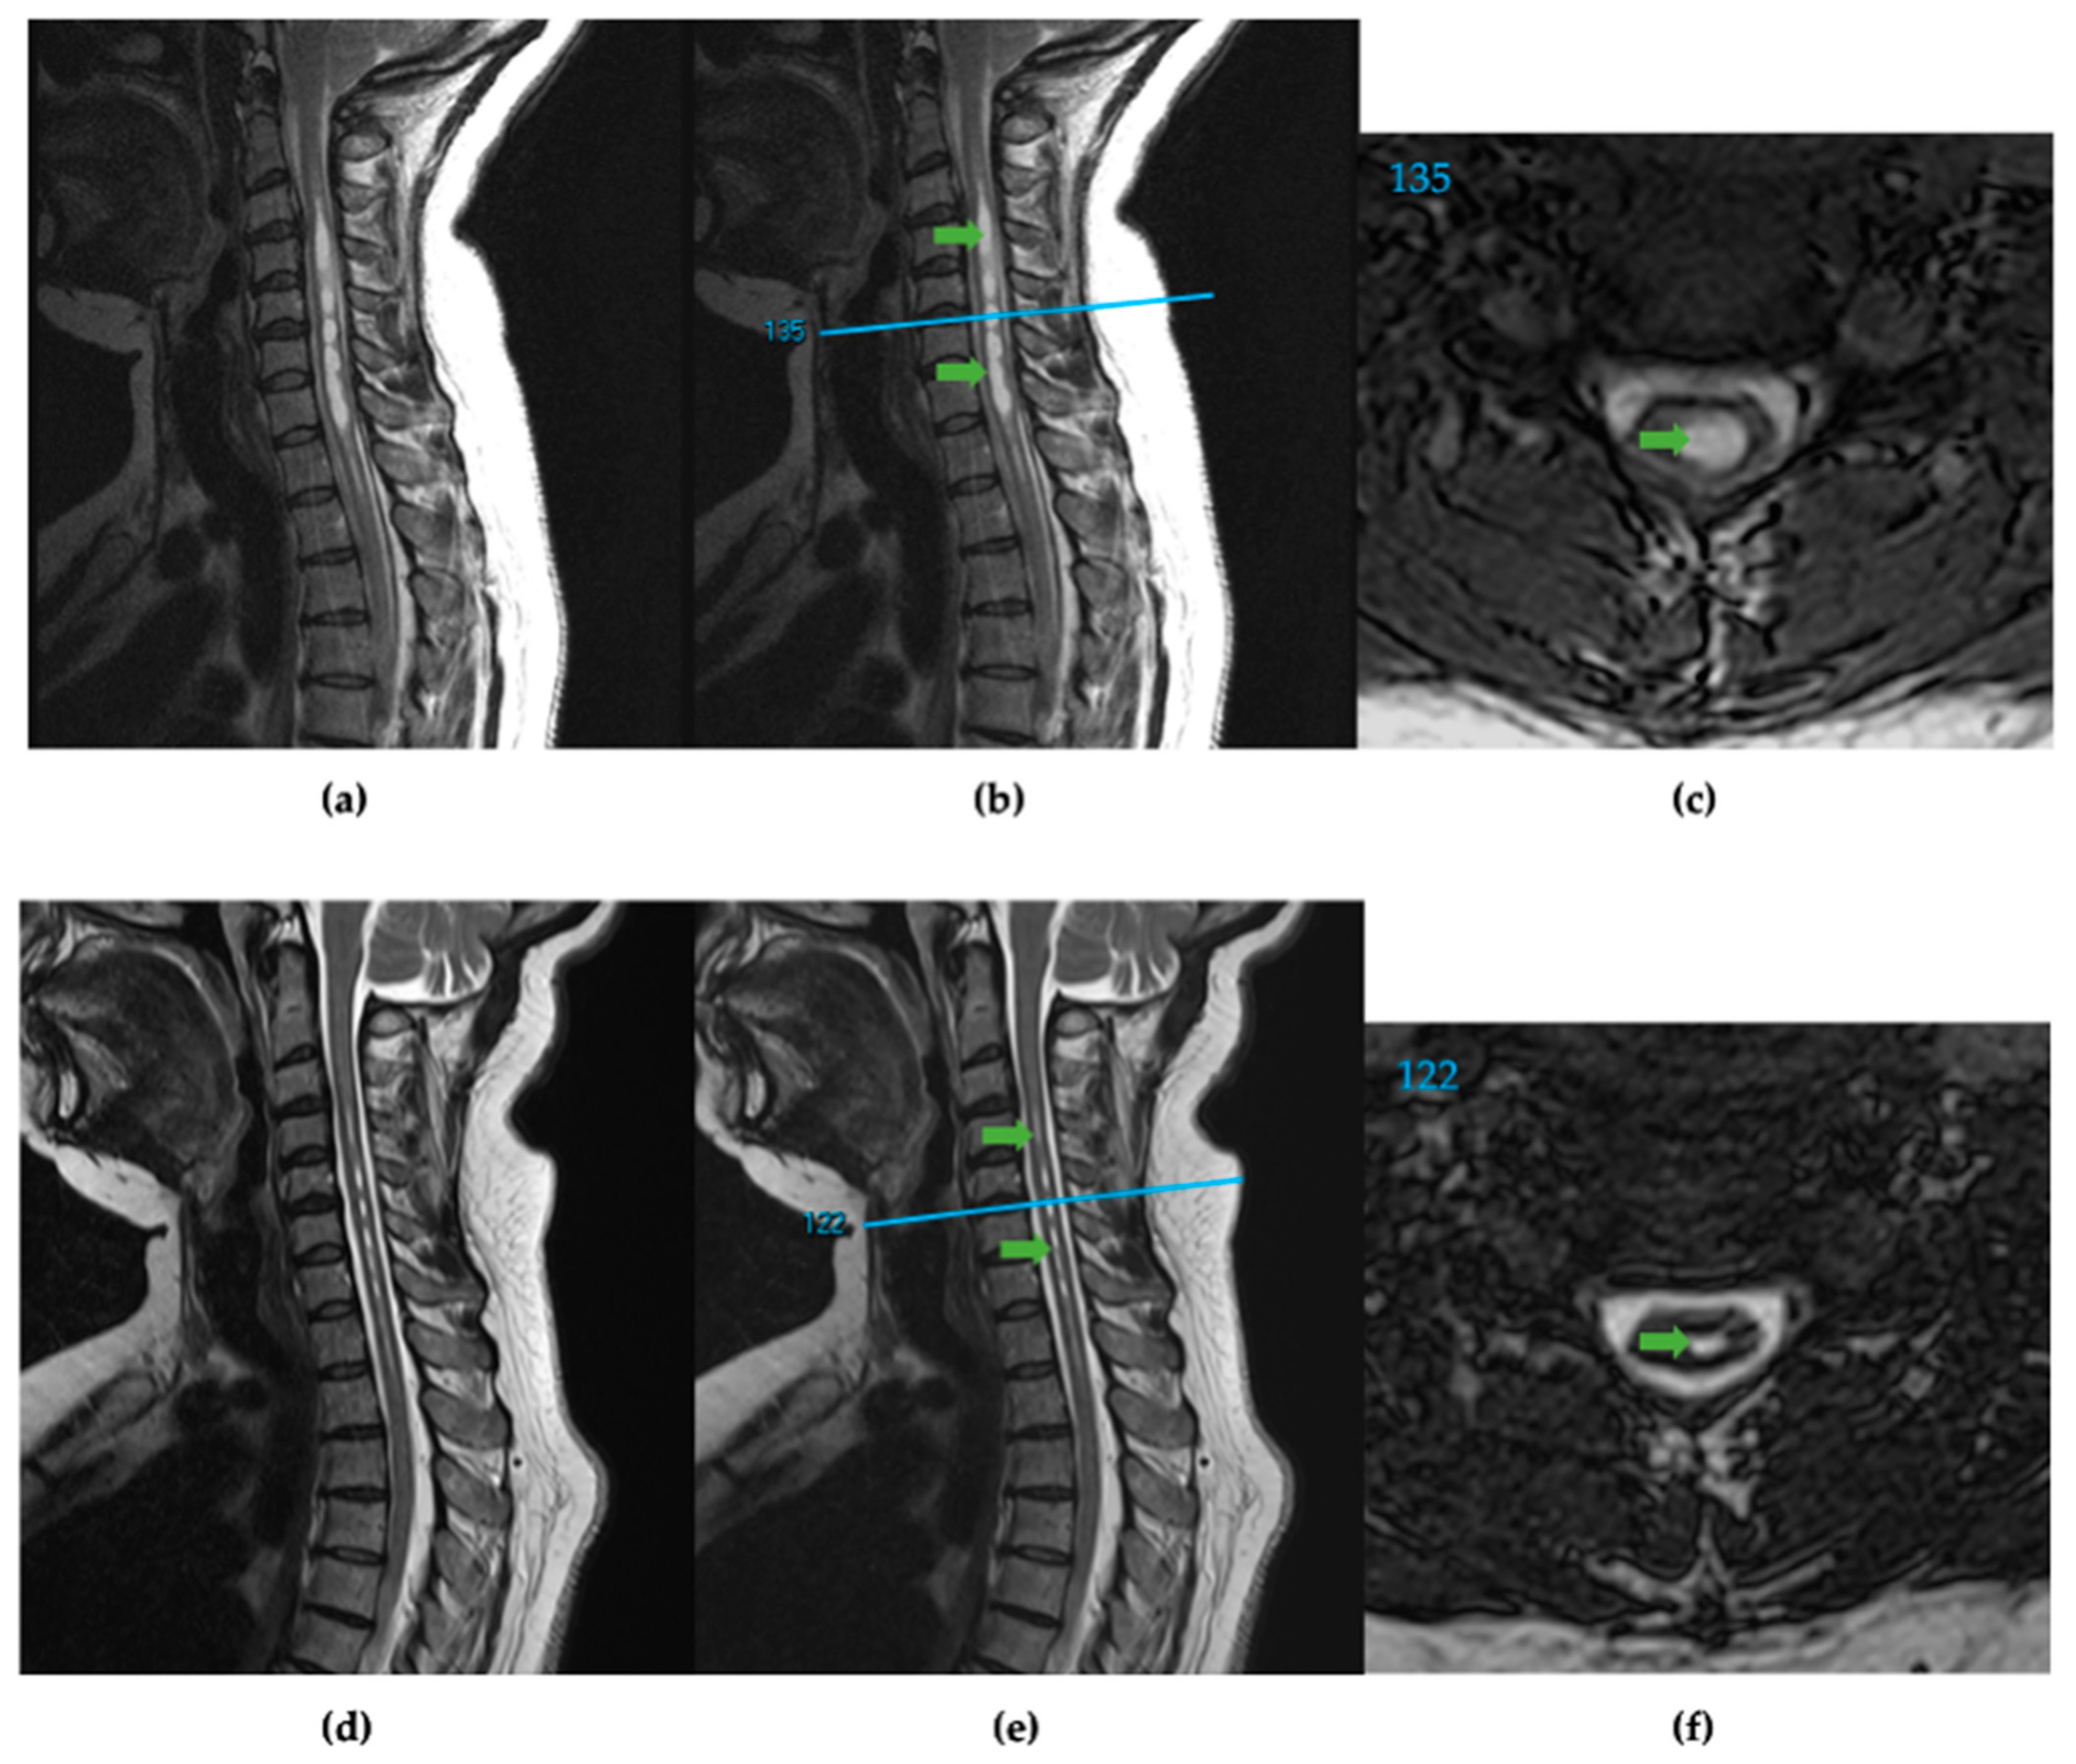

2.2. Manual Cavalieri Method (CAV) of Analysis

2.3. Spinal Cord Analysis Tool (SCAT) Method of Analysis